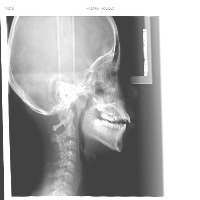

cepha lo Computer Vision Project

Classes (15)

Landmarks are annotated in COCO format.

The dataset includes 1700 images.

landmarking3 - v1 2022-09-02 2:23pm